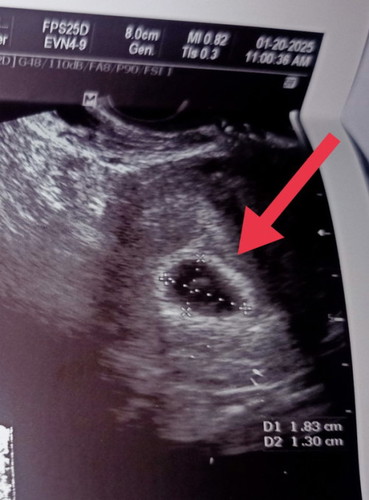

normal lang po ba na no embryo? 6wks and 1 day npo me nung nag pa check up sa ob ko.monday po FU ko.

no embryo @6weeks & one day. just only Sac.